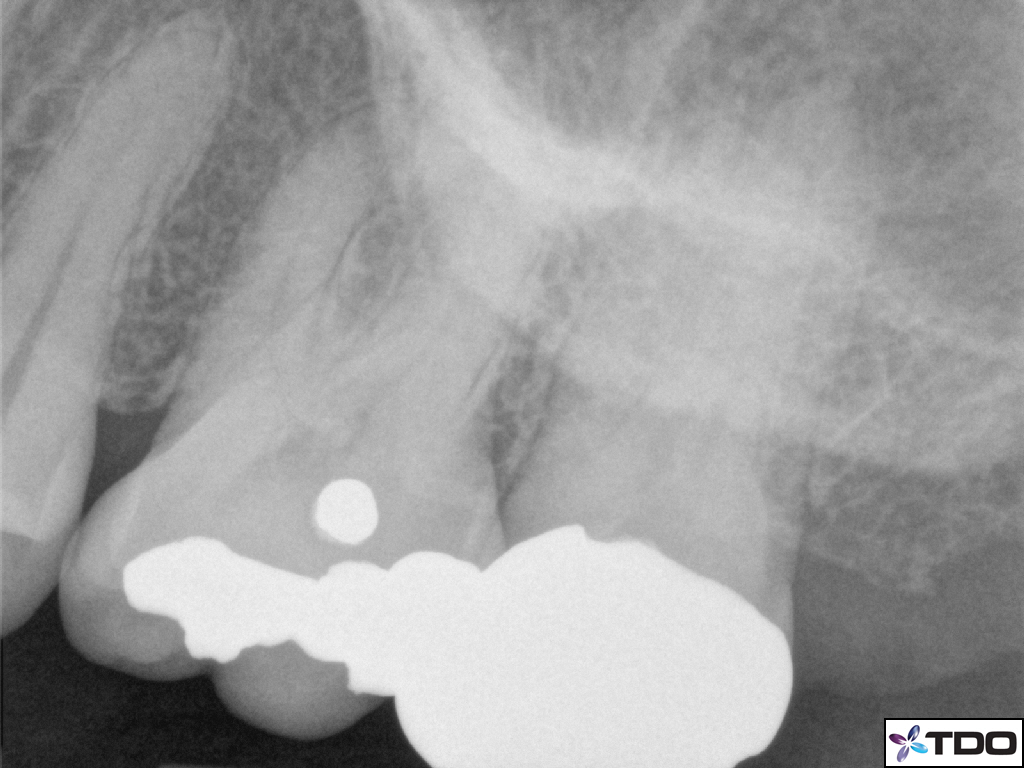

Amalgam Restoration Radiograph . download scientific diagram | radiograph of amalgam (tooth no. radiopacity enables clinicians to assess restoration integrity, to observe the restoration margins to diagnose. radiographic images of amalgam have been used in dental forensics for identification due to their unique appearance. the radiopacity of restorative materials is particularly important for radiographic diagnoses 1 because. clinical photograph and bitewing radiograph of a large amalgam restoration in tooth 16, considered as failed due to a fractured. this paper will give an overview of general matrix problems when restoring amalgam restorations for primary molars. Amalgam fillings were placed in 40 typodont teeth, the surface areas of the restorations were determined by. 15) and composite restoration (tooth no.

download scientific diagram | radiograph of amalgam (tooth no. Amalgam fillings were placed in 40 typodont teeth, the surface areas of the restorations were determined by. radiopacity enables clinicians to assess restoration integrity, to observe the restoration margins to diagnose. this paper will give an overview of general matrix problems when restoring amalgam restorations for primary molars. clinical photograph and bitewing radiograph of a large amalgam restoration in tooth 16, considered as failed due to a fractured. the radiopacity of restorative materials is particularly important for radiographic diagnoses 1 because. radiographic images of amalgam have been used in dental forensics for identification due to their unique appearance. 15) and composite restoration (tooth no.

Amalgam Restoration Radiograph the radiopacity of restorative materials is particularly important for radiographic diagnoses 1 because. radiographic images of amalgam have been used in dental forensics for identification due to their unique appearance. clinical photograph and bitewing radiograph of a large amalgam restoration in tooth 16, considered as failed due to a fractured. radiopacity enables clinicians to assess restoration integrity, to observe the restoration margins to diagnose. download scientific diagram | radiograph of amalgam (tooth no. this paper will give an overview of general matrix problems when restoring amalgam restorations for primary molars. the radiopacity of restorative materials is particularly important for radiographic diagnoses 1 because. 15) and composite restoration (tooth no. Amalgam fillings were placed in 40 typodont teeth, the surface areas of the restorations were determined by.